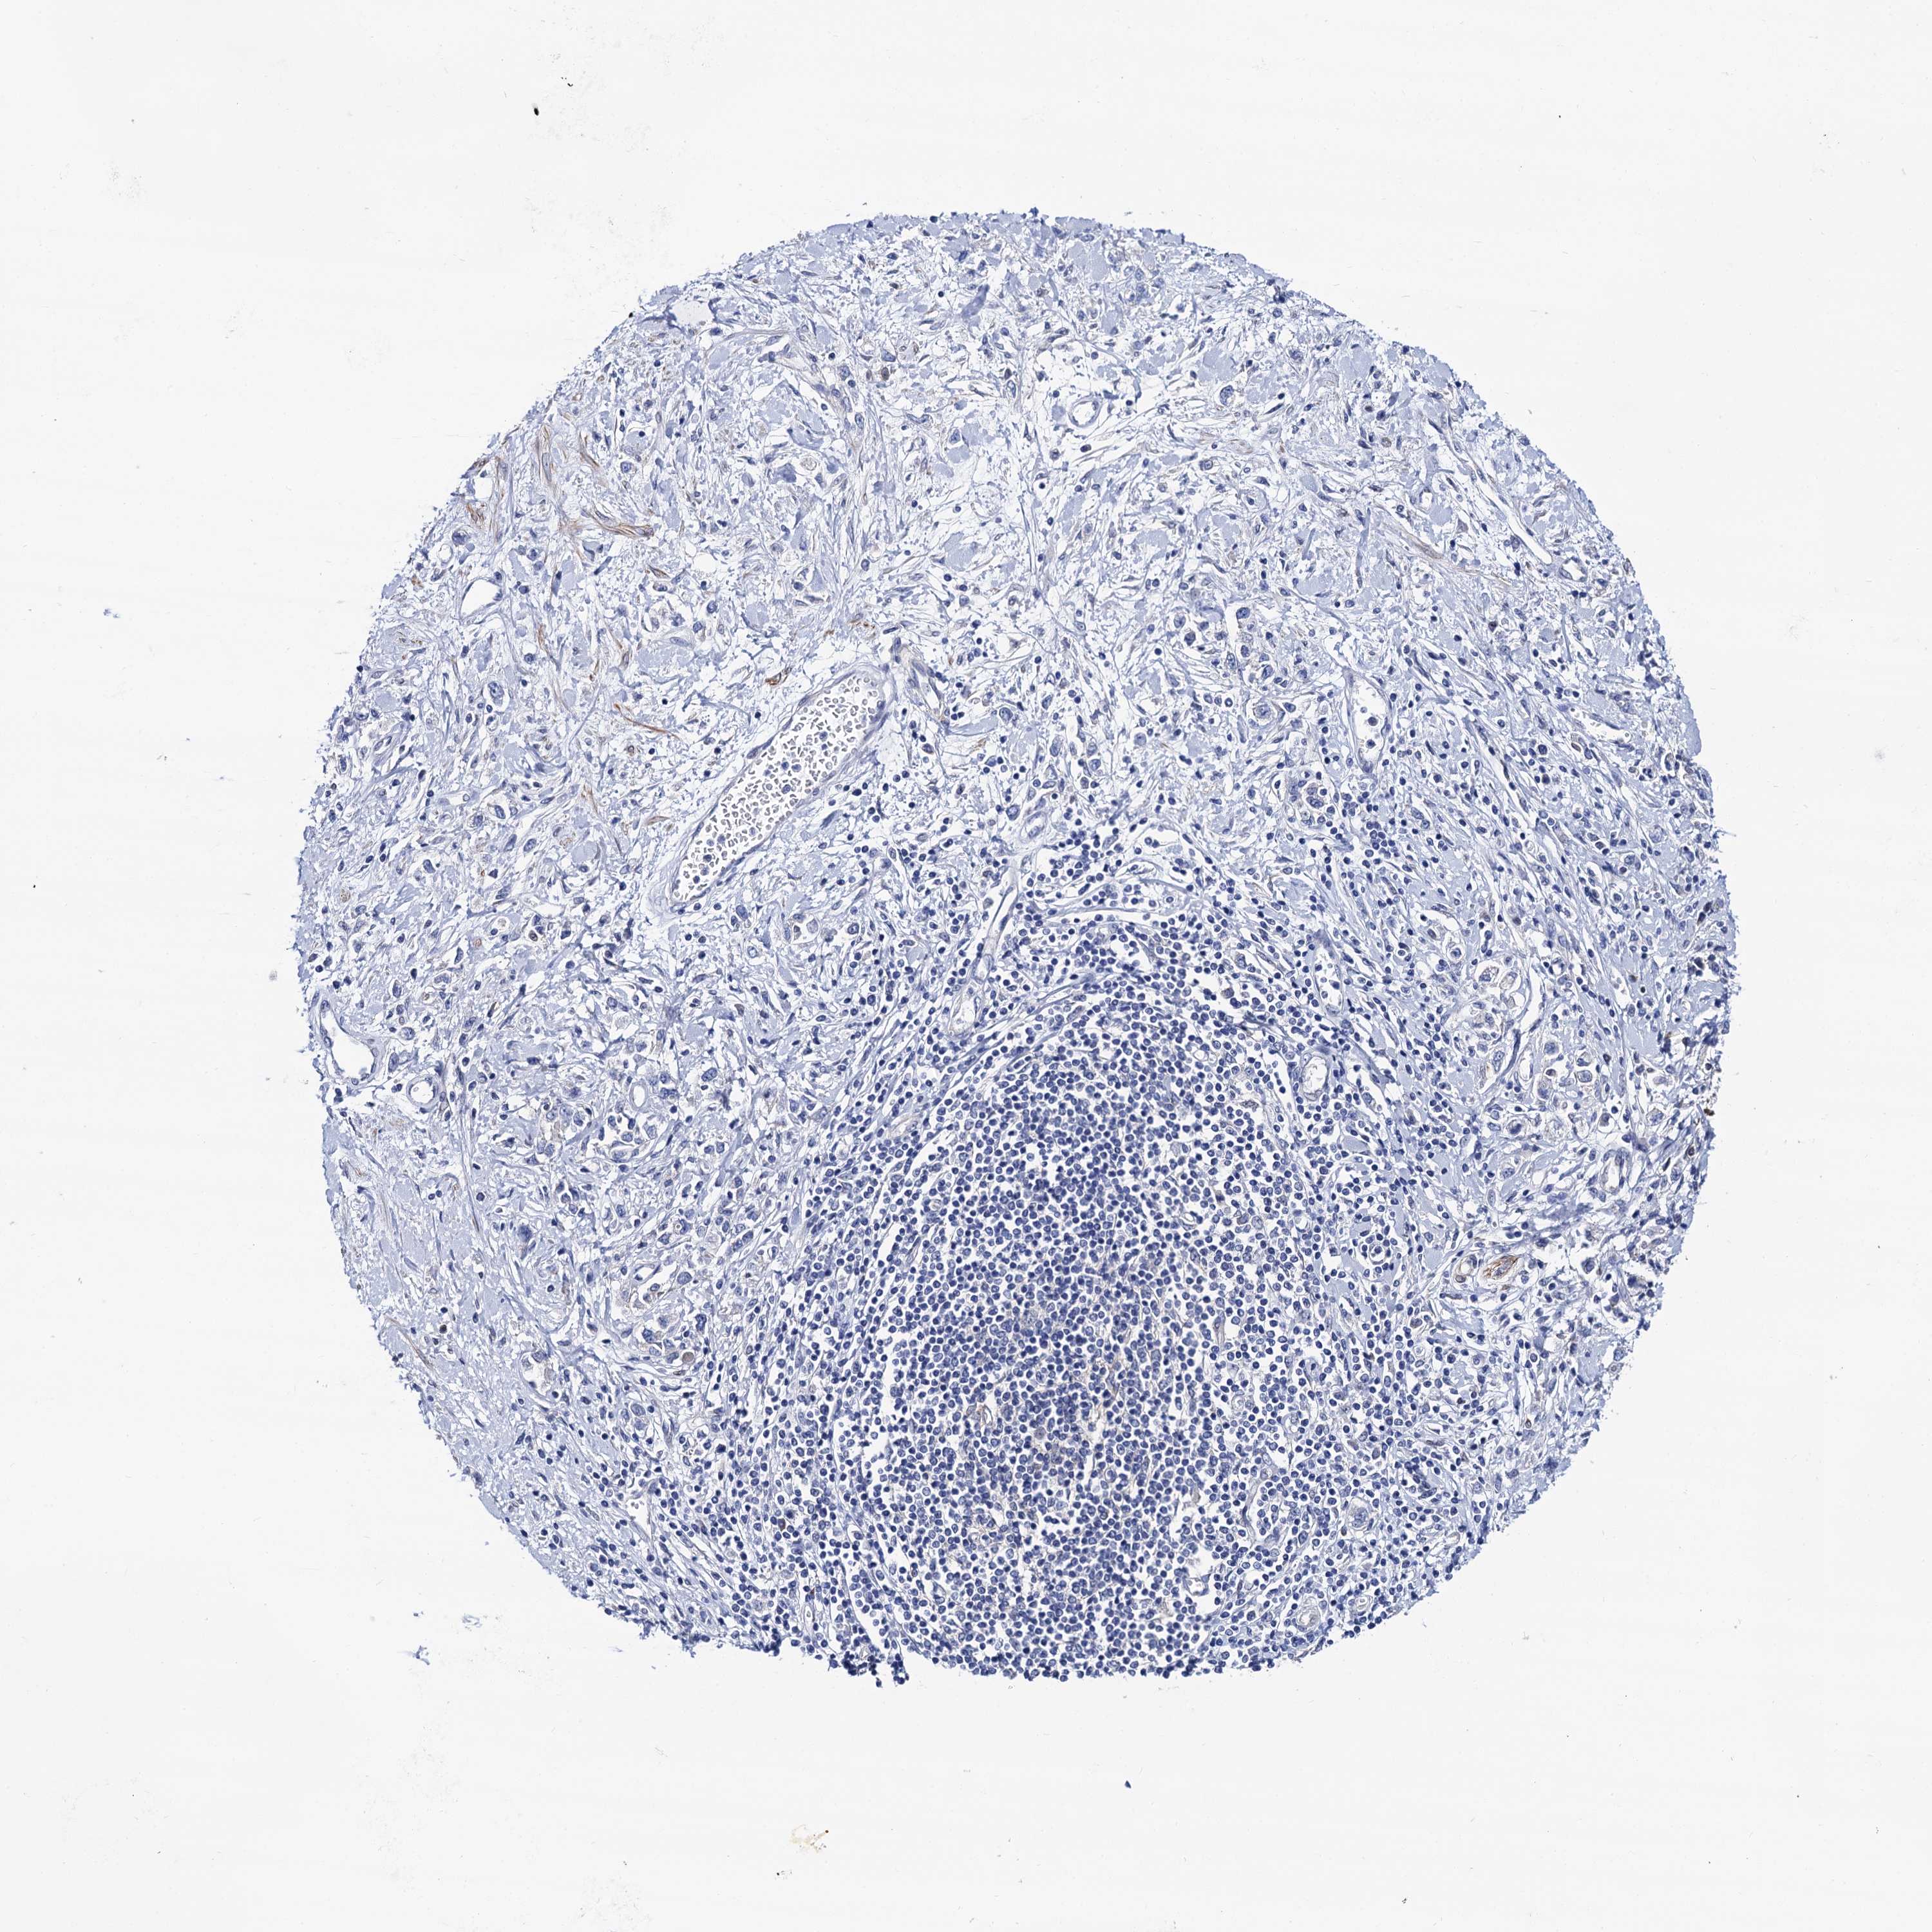

STOMACH CANCER - Protein expressioni

A mouse-over function shows sample information and annotation data. Click on an image to view it in a full screen mode. Samples can be filtered based on level of antibody staining by selecting one or several of the following categories: high, medium, low and not detected. The assay and annotation is described here.

Note that samples used for immunohistochemistry by the Human Protein Atlas do not correspond to samples in the TCGA dataset.

Antibody stainingi

Antibody staining in the annotated cell types in the current human tissue is reported as not detected, low, medium, or high, based on conventional immunohistochemistry profiling in selected tissues. This score is based on the combination of the staining intensity and fraction of stained cells.

Each image is clickable and will lead to virtual microscopy that enables deeper exploration of all samples and also displays staining intensity scores, fraction scores and subcellular localization as well as patient and tissue information for each sample.

Antibody HPA040234

Staining

High

Medium

Low

Not detected

Intensity

Strong

Moderate

Weak

Negative

Quantity

>75%

75%-25%

<25%

None

Location

Nuclear

Cytoplasmic/membranous

Cytoplasmic/membranous,nuclear

Adenocarcinoma, NOS